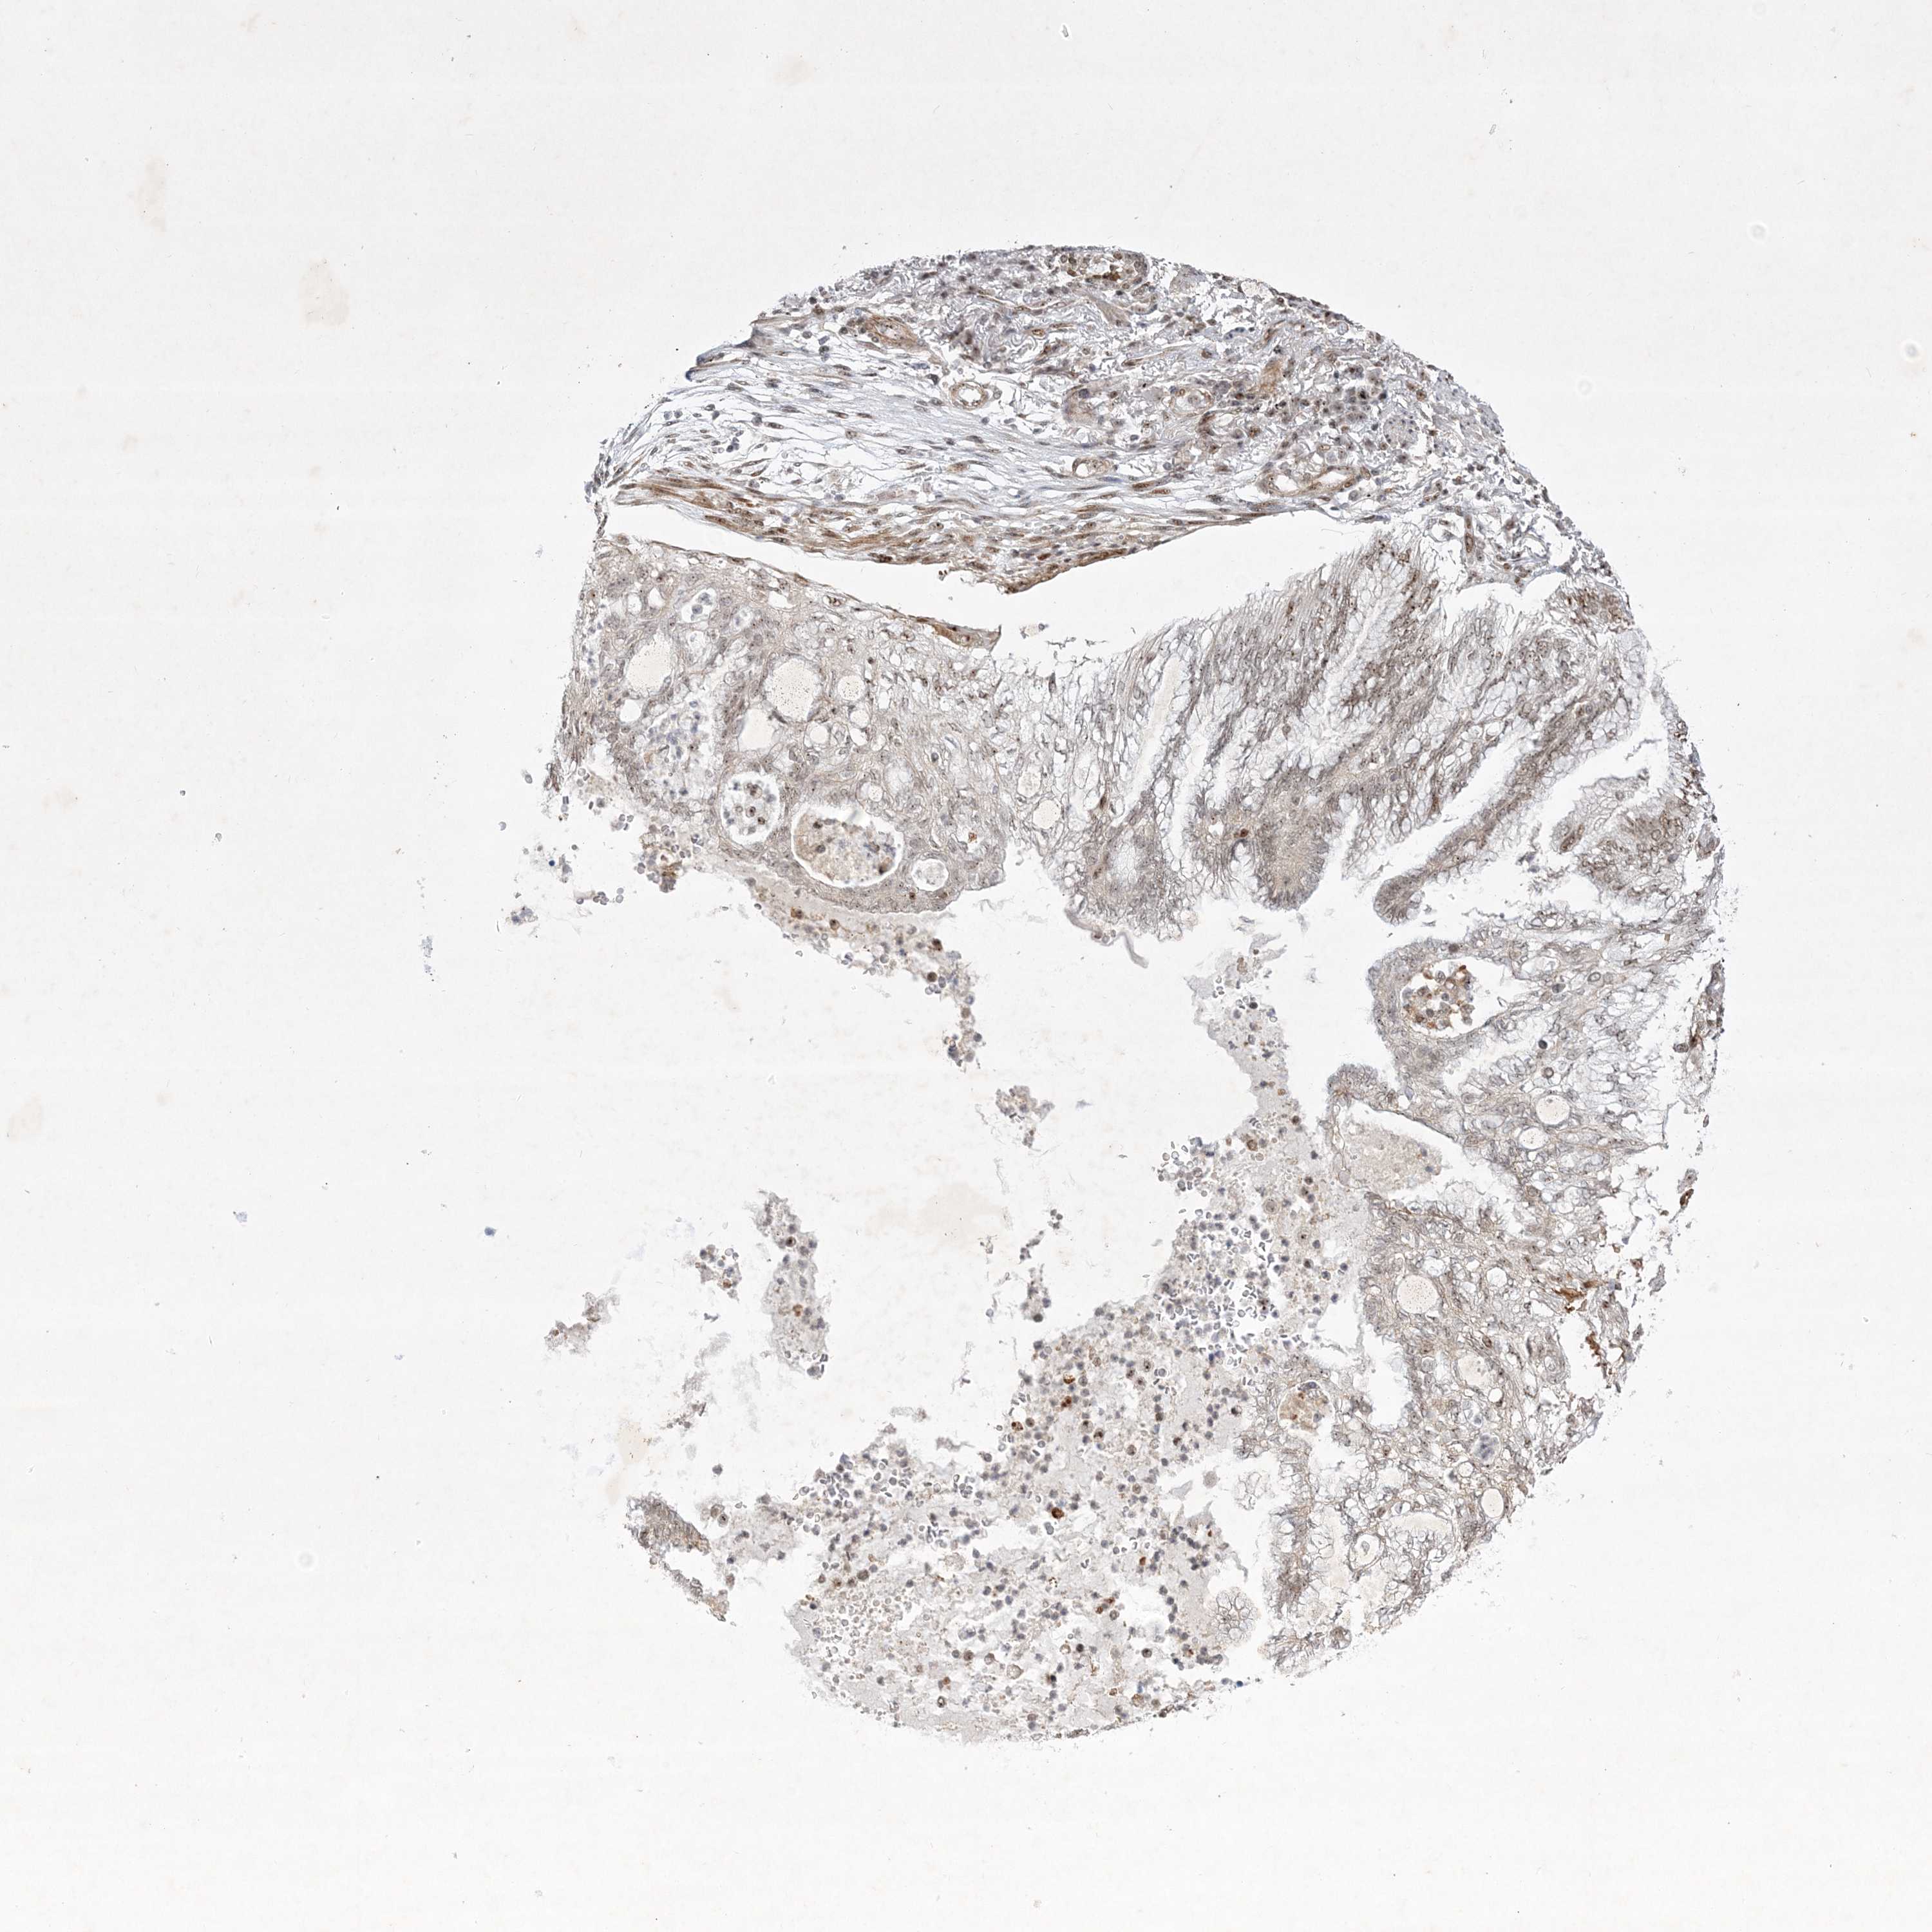

CANCER LUNG CANCER Show tissue menu

LUAD TCGA LUAD VALIDATION LUSC TCGA LUSC VALIDATION PROTEIN LUAD CPTAC PROTEIN LUSC CPTAC PROTEIN EXPRESSION

ANTIBODIES

AND

VALIDATION